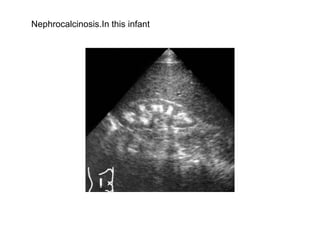

Nephrocalcinosis.Early nephrocalcinosis  causes an echo dense rim around the pyramids.

Nephrocalcinosis.In this infant